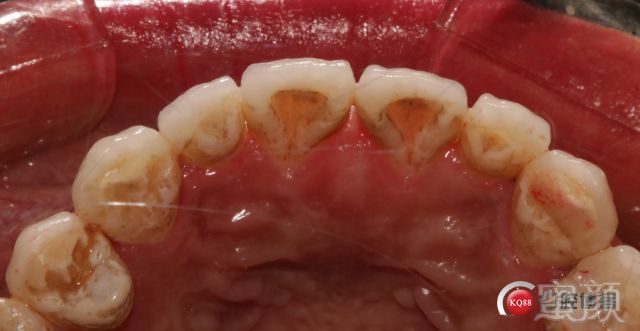

唯一的调整是因为去除树脂后切端的牙体发黑所以从开窗式的修复方案改为对接式。包绕式。

粘接式非常痛苦的过程~~~省略一万个字,上橡皮章排龈,非常费时。

下颌我要等技工室的全合架到位了再做;因为涉及到几个合位关系的确定问题;下颌要采用对接式所以侧方合关系要特别注意,不然会出问题。患者很满意;中缝黑三角2周后应该可以恢复;排龈时间压得有点长;两单位对称粘接;邻间隙一定要能过牙线,再往下做;手术刀慢慢刮还是有点费力。效果不错患者满意。